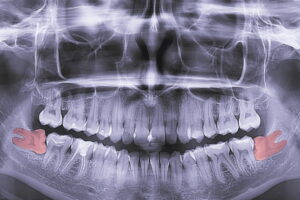

2023年6月30日 / 最終更新日 : 2023年6月30日 tom x-ray of teeth, molar tooth improperly growing, absence of the eighth molar